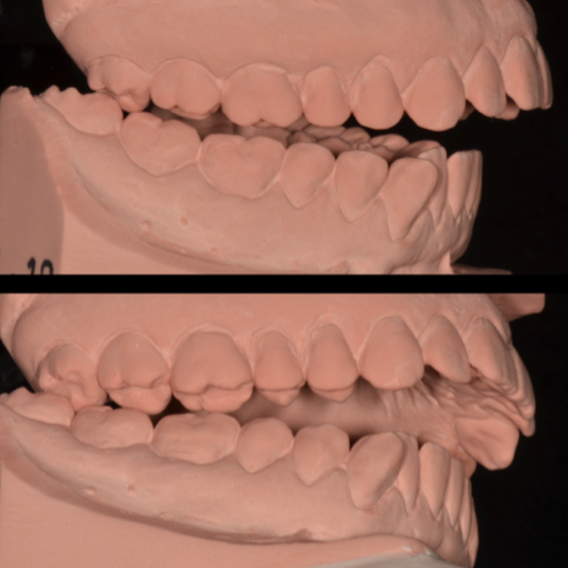

CASE STUDY

Complex Case Handled with nexo

Treatment of lower crowding using the FACE Philosophy FAS aligner system with posterior corticotomies. The arch form was modified, achieving FACE treatment goals in 220 days. The case included a first phase with 20 FAS Hard track® aligners (5-day changes) and a second phase with 12 Soft track® aligners (10-day changes), using intra-treatment scans to plan each stage.